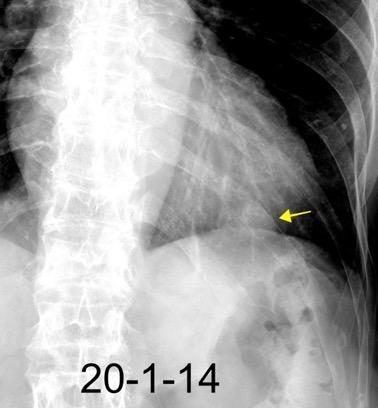

29. FALSA ELEVACIÓN DIAFRAGMÁTICA. GRASA

Grasa simulando elevación diafragmática izquierda